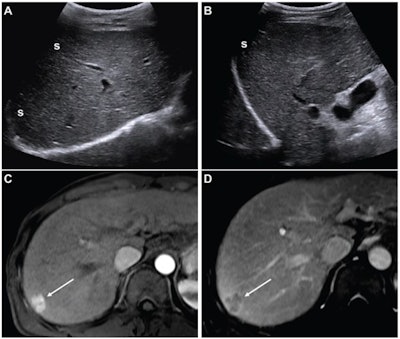

(A,B) Images from an initial ultrasound examination showed no identifiable lesions and received a consensus ultrasound category of US-1. Nearly the entire liver is visualized, with minimal shadowing (“s”, A and B), and the examination received consensus result of VIS-A. The AFP level was 7.1 ng/mL on assessment six months before the ultrasound, 9.1 ng/mL on assessment three months before examination, and 14.2 ng/mL on assessment on exam day. The AFP result was thus assessed as positive based on a progressive increase on two consecutive tests. The atient was considered to have negative surveillance result according to LI-RADS Ultrasound Surveillance v2017, but positive surveillance result according to LI-RADS Ultrasound Surveillance v2024. (C-D) Axial arterial-phase (C) and portal-venous phase (D) T1-weighted images from subsequent gadoxetic acid-enhanced MRI show a 2-cm arterial-phase hyperenhancing observation (arrow, C) with portal-venous washout (arrow, D) in segment 7. This observation was classified on MRI as LR-5, thus meeting the present study’s reference standard for diagnosis of HCC. The mass is located in the periphery of the liver, an anatomic area where ultrasound visualization can be challenging due to shadowing.ARRS